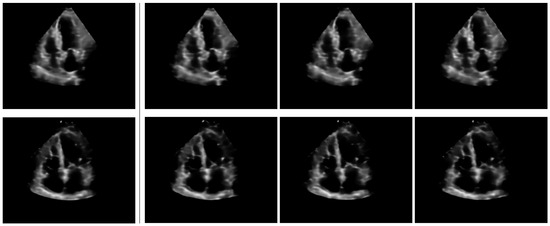

For instance retrieval, nearest-neighbor matching based on the Euclidean distance between descriptors can be employed. Initially, we conduct a qualitative analysis by randomly sampling images from the test set and manually selecting specific query points to analyze the results. The descriptors corresponding to these selected query points were then used to search the database and retrieve samples with regions similar to the query points. Figure 5 showcases six randomly sampled examples, which illustrate that the retrieved image regions align well with the query semantics. For example, the retrieved regions share the same cardiac chamber and view as the query points. Moreover, the anatomical structures around the matched locations are visually similar to those in the query points.

Figure 5.

Region-based instance retrieval using conceptual search. The leftmost column displays query images, while the last three columns show the top-3 kNN retrieval results. Red dots indicate the centers of the query and matched descriptor regions. Below each image, the view and cardiac phase are displayed. Matches marked with an asterisk (*) are from the same acquisition as the query image, but from a different cardiac phase.

For the retrieval task, the search is based solely on the concept descriptors This approach ensures that the retrieval process focuses on the semantic content rather than stylistic variations.